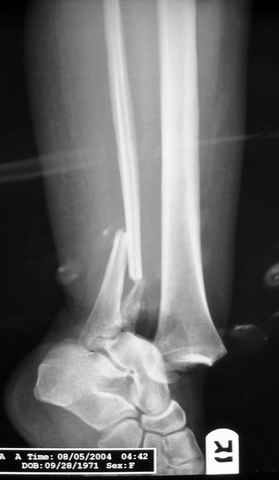

Pilon fracture:

ET> ЕЧ При подобных переломах фиксация малоберцовой кости обеспечивает

ET> низведение латерального тибиального фрагмента - появляется ориентир для

-Появляется ориентир и остов, на чем можно строить восстановление, почему сперва малоберцовую, впервые обьяснили и описали (Pylon type and Ankle fractures) в середине 50х Rienau и Gay.

Восстановливая длину и ротацию малоберцовой кости, затем относительно легче произвести реставрацию остальных элементов перелома дистального эпиметафиза болшеберцовой кости.

где исследования на трупах показали, что малоберцовая кость участвует в стабильности голеностопного сустава, поддерживая наклон тарана (talar tilt) за счет связок. После ознакомления работой Ramsey в ортопедию ввели термин "при переломах голеностопного сустава смещенная

таранная кость следует за малоберцовой костью" т.е. связка не рвется, а тянет таран за собой, поэтому восстановление малоберцовой кости в

первую очередь, затем остальных элементов - стал классическим при лечении данной патолгии. Латеральная колонна (столб), дистальный

конец малоберцевой кости, к нему прикрепляется латеральный суставной фрагмент дистального эпиметафиза большеберцовой кости (как на снимке)

и таранная кость, которые при репозиции малоберцовой кости репонируются автоматически.